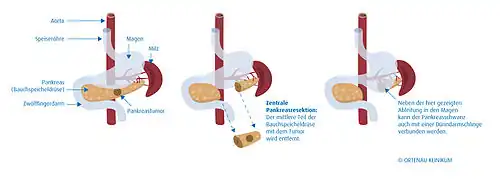

Es ist sinnvoll, möglichst einen Teil des Organs zu erhalten und wieder mit dem Darm zu verbinden. Je nach Ort des Tumors wird deshalb die rechtsseitige Teilresektion (Duodenopankreatektomie, mehrere Varianten), eine mittlere Teilresektion, eine linksseitige Teilresektion (Pankreasschwanzresektion, meist mit Entfernung der Milz) oder eine Totalresektion (vollständige Entfernung) der Bauchspeicheldrüse durchgeführt, meist einschließlich aller regionären Lymphknoten. Der Magen und der Gallengang müssen wieder mit dem Darm verbunden werden. Man verwendet dafür entweder eine oder mehrere hochgezogene Dünndarmschlingen, die spannungsfrei angeschlossen werden. Bei der Verwendung mehrerer Dünndarmschlingen werden diese rekonstruiert nach der klassischen von César Roux erdachten Methode. Nach Teilresektion kann der Ausführungsgang des belassenen Rests der Bauchspeicheldrüse sowohl mit dem Dünndarm als auch mit dem Magen verbunden werden.

Mit einer Segmentresektion werden definierte Teile der Bauchspeicheldrüse entfernt: entweder der Kopf einschließlich Zwölffingerdarm, der mittlere (zentrale) Abschnitt oder der linksseitige Teil. Die Milz kann mit entfernt oder bei geeigneten Fällen belassen werden. Vom Ausführungsgang abgeschnittenes Gewebe muss entweder in eine nach Roux Y-förmig (d. h. end-zu-seit-) angenähte Dünndarmschlinge oder in den Magen drainiert werden.